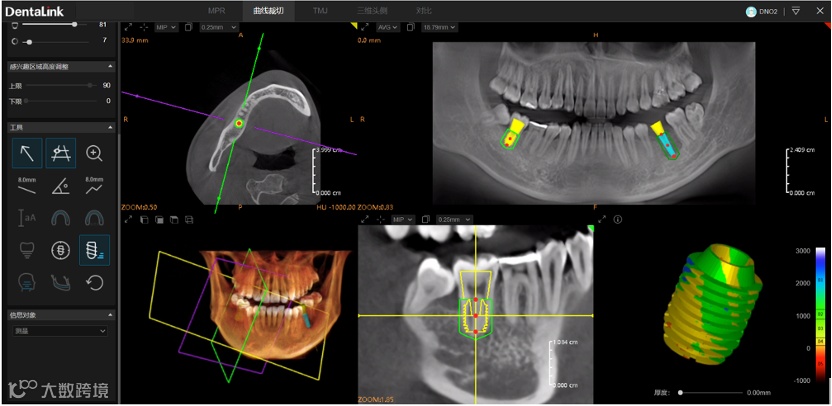

1)植体放置&红色预警

2)植体周围360度旋转检查

3)植体周围骨密度检查